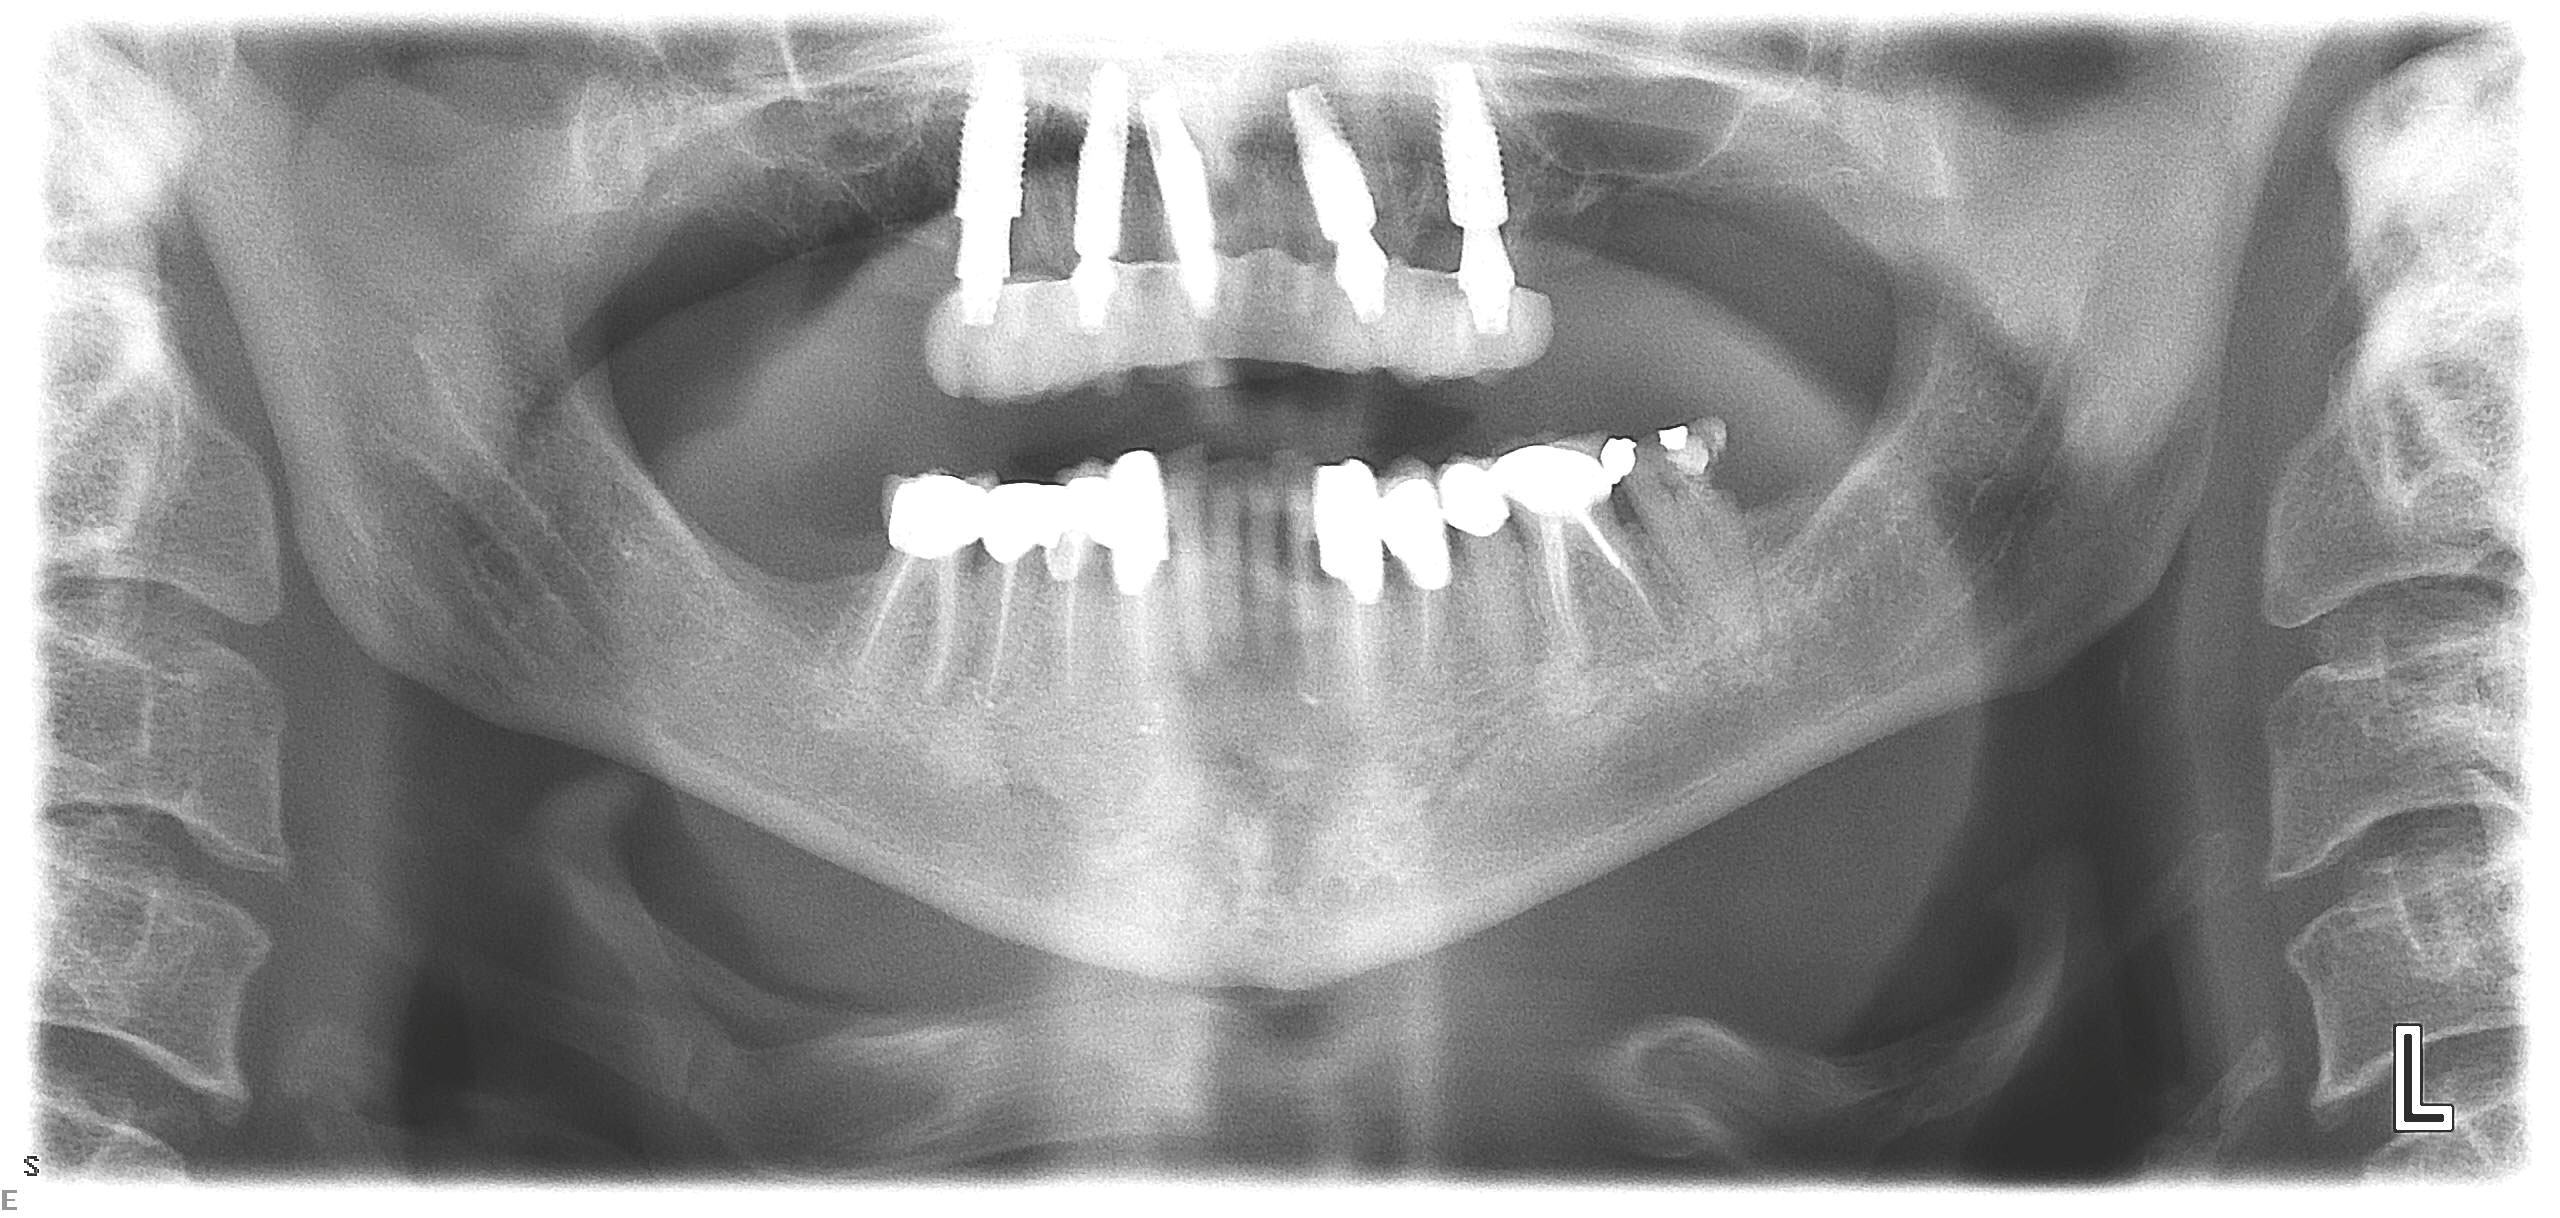

Fig 11. Initial panoramic radiograph.

Figure 11

A 60-year-old female patient presented with many periodontally and restoratively hopeless teeth that severely compromised esthetics and function and were inadequate to retain a maxillary restoration. She declined to advance into a full maxillary denture or partial denture. Existing maxillary teeth included Nos. 2 and 4 through 14 (Figure 9 and Figure 10). The opposing dentition was stable. The patient was in good health with no allergies to medication.

At the initial visit, a panoramic x-ray (Figure 11) and periapical x-rays were taken. The patient was photographed to capture her full face and shoulders, and a digital scan of the maxillary dentition was obtained. This file was electronically sent to the implant company to complete the VSD.